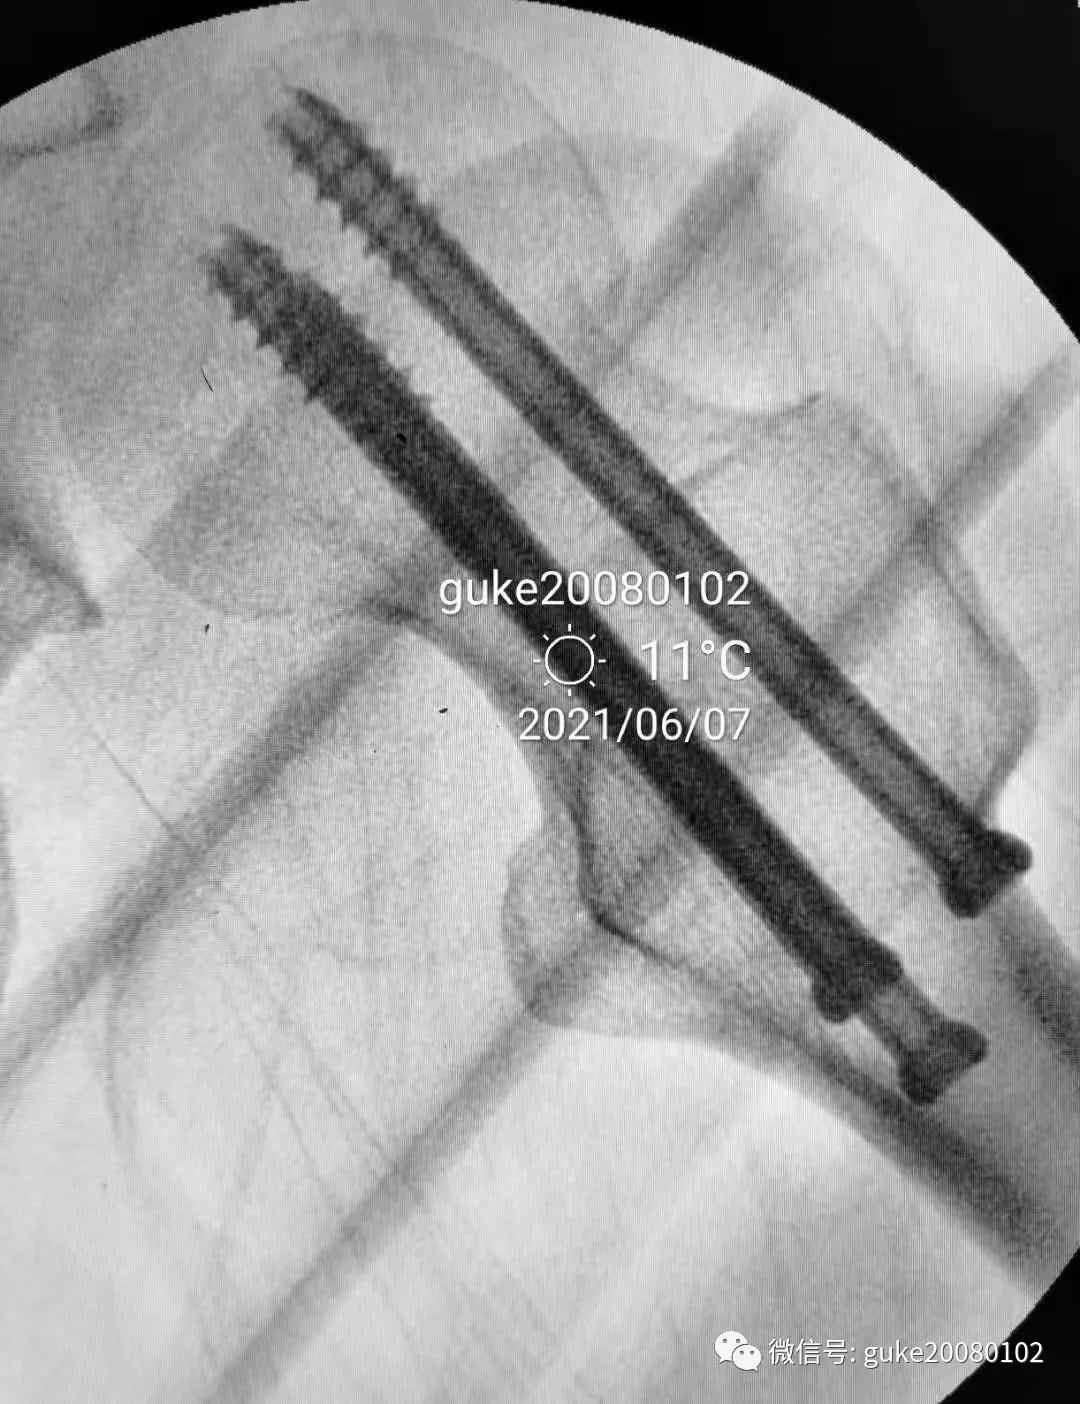

1.正侧位观察骨折复位,骨小梁走形恢复。崁插骨折复位。

2.外侧植入克氏针一枚,临时固定骨折。